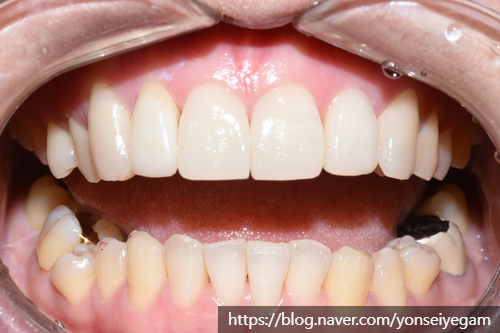

![[시청역/광화문/서대문]삐뚤삐뚤한 치아 무삭제라미네이트로 치아성형 관련 이미지 3](https://pub-9f2bb3498faf4d1d8714b41df24753e3.r2.dev/content/clinics/archive/rseeanjxfu/naver_blog/yonseiyegam/assets/by_hash/1fc1c1b786ecf3b987366d9163a971377438120af1a16720c8aaa665a9b61416.jpg)

입천장쪽에서 찍은 사진을 보면 치아가 굉장히 삐뚤빼뚤한 것을 볼 수 있습니다.

단, 이 케이스에서 화살표의 치아는 너무 많이 튀어 나와있었으므로

이 치아만 삭제를 진행하여 라미네이트가 아닌 크라운으로 진행하였습니다.